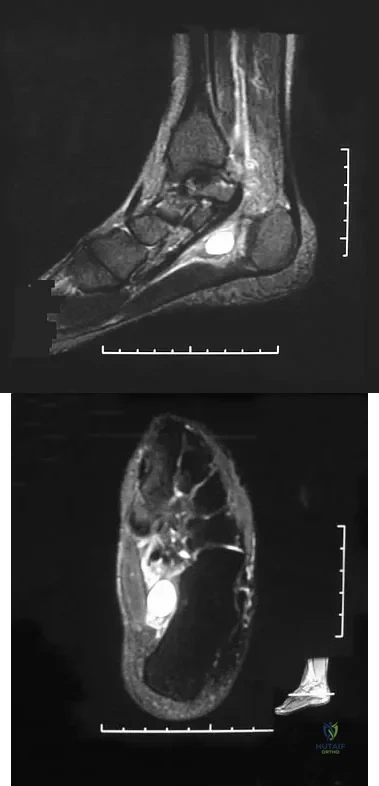

Question 40

A 47-year-old woman has had medial ankle pain and swelling for the past 3 months. She recalls no specific injury, and casting and nonsteroidal anti-inflammatory drugs have failed to provide relief. Examination reveals a pes planus with heel valgus that is passively correctable. Radiographs show no evidence of arthritis. An MRI scan is shown in Figure 16. What is the most appropriate surgical procedure to alleviate her pain?

Explanation

Question 41